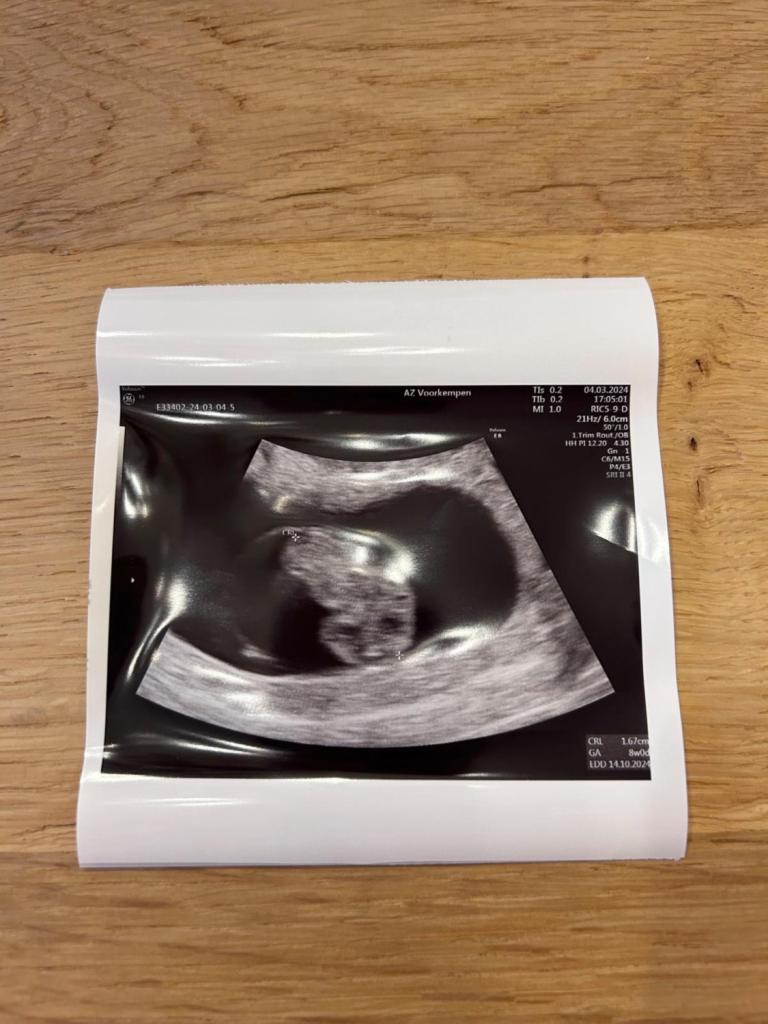

Première échographie

« La première échographie a marqué le début de notre aventure. À ce moment-là, nous rêvions déjà de notre petite famille à 4. »